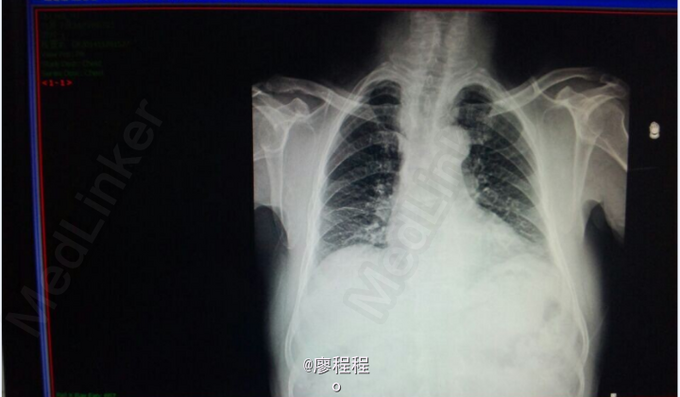

患者男,31岁。 主诉:间断胸闷气促3年,加重1天。 现病史:患者于3年前无明显诱因出现活动后胸闷、气促,于我院诊断为“致密化不全心肌病 二尖瓣关闭不全 左心扩大“,治疗好转后出院,此后规律随访,无特殊不适。于2015.04.01日-04.12日(2月前)再次因胸闷气促加重来我院就诊,病情好转后出院。患者于昨日开始无明显诱因上述症状再次出现,感气促、胸闷,时有干呕,伴心悸、乏力、纳差,来我院途中持续性发作胸口正中处疼痛约20分钟,未服药逐渐缓解,无发热、咳嗽咳痰、黑朦、晕厥、肢体水肿等异常。自起病以来,患者精神、饮食、睡眠欠佳,小便量一般,大便如常,体重未见明显改变,活动耐力明显下降。既往有心律失常发作、乙肝病史4余年,余无特殊。

查体:生命体征平稳,神清,唇红,颈静脉无充盈,心音低钝,心尖部闻及收缩期吹风样杂音,双肺呼吸音稍粗,余查体无特殊。 辅助检查:胸部正位X线

初步诊断: 扩张型心肌病 全心增大 二尖瓣重度关闭不全 心功能Ⅲ级 处理:1、完善血、尿常规、肝肾功能、BNP等检查; 2、给予强心、利尿、抗凝、抗心肌重构等对症支持治疗; 3、密切观察病情变化,根据病情及时处理。